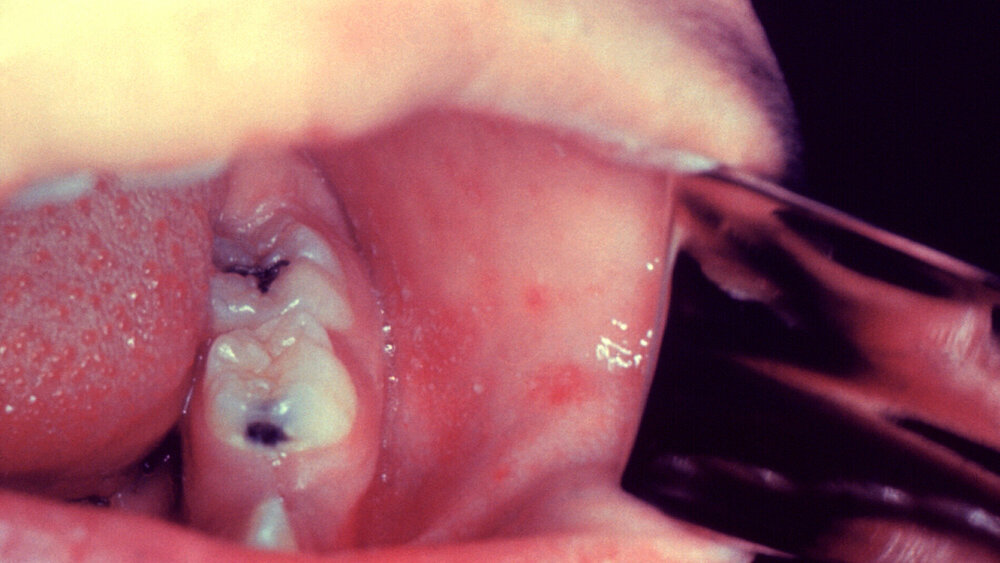

Während der prodromalen Phase der Virusinfektion haben die Patienten häufig Fieber, keinen Appetit, einen trockenen Husten und sind müde. Ebenfalls beschrieben sind prominenter Nasenausfluss, Photophobie in Folge einer Konjunktivitis, Sklerarötung und Schwellung der Augenlider. Die charakteristischen Koplik-Flecken treten in dieser Phase als winzige, weiße oder graue Punkte auf, die von einem roten Halo umgeben sind und oft auf der Mundschleimhaut in der Nähe der Molaren erscheinen. Sie ähneln verstreuten Kalktropfen und sind pathognomonisch für Masern.